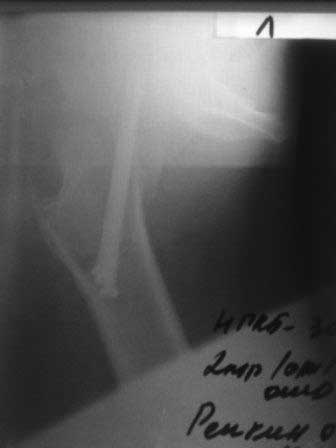

Уважаемые коллеги! Обратился б-ной около 40 лет, три месяца назад оперирован в г.Алмате. При осмотре - ходит c двумя костылями, беспокоят постоянные боли, симптом прилипшей пятки положительный, посмотрел под Р-скопией; сращения нет. Понимаю, показано эндопротезирование, но можно ли органосохраняющие операции с аутопластикой? Если можно, примеры из практики! С уважением Абдурашид. P.S. Р-снимки сразу после операции, и вчерашные.

В данное время важно установить точный диагноз: есть ли замедленное сращение или ложный сустав? Сколько надо ждать 6-12 месяцев? Из 67% сросшихся переломов шейки бедра в 14% переломы срослись через 6 мес.

Появление внезапных болей после 2х месяцев на фоне успешного послеоперационного течения процесса является клиническим сигналом о проблеме в суставе.

Но подозрение надо доказать более обьективными данными и мы ориентируемся на изменения позиции шурупов от первончального на 5 градусов, выступание более чем 20 мм и изменения репозиции на 10мм.